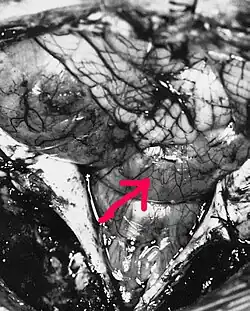

Удаление эпендимом спинного мозга производится с применением заднего доступа. После ламинэктомии (удаления задних отделов позвоночника) вскрывается твёрдая мозговая оболочка. Срединный разрез спинного мозга над тканью эпендимомы позволяет её визуализировать. После этого производится по возможности тотальное удаление новообразования[40].